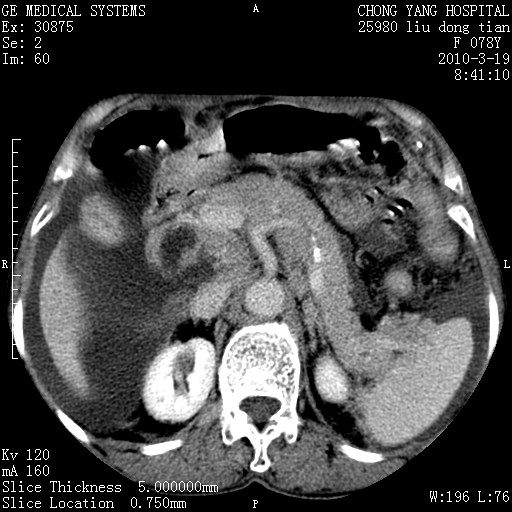

标题: CT25199:F 78Y 腹胀半年 消瘦乏力 [打印本页]

考虑nhl,肝、脾、腹膜腔及腹膜后多发淋巴结受侵,腹水,右肾囊肿,慢性胆囊炎,右侧少量胸腔积液。

分开来讲:肝左叶、尾叶病灶有不均强化像肝癌;

脾脏病灶无强化,像多发囊肿或淋巴管瘤,不除外淋巴瘤(低强化);

肝门、胰腺头、腹膜后多个团块: 淋巴瘤,转移;

脾脏病灶像车轮 莲花,第一感觉还像包虫呢。真想全切出来一个个做病检。

最后报的胰头癌多发转移,脾脏单独考虑囊肿或淋巴管瘤。